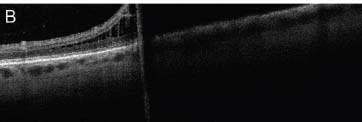

Alternatively, the pathology of interest may not be located within the macula. While OCT is well suited for systems display the position of the scan on a high-reso-macular imaging, it can also be targeted peripherally. For lution scanning laser ophthalmoscopy (SLO) image. This example, in a patient with bullous retinal elevation, peripheral OCT can distinguish between retinal detachment and retinoschisis, affecting the decision to recommend surgery or observation (Figure 3, page 50).

Figure 3. Peripherally directed OCT scans are useful in distinguishing between retinal detachment (A) and retinoschisis (B).